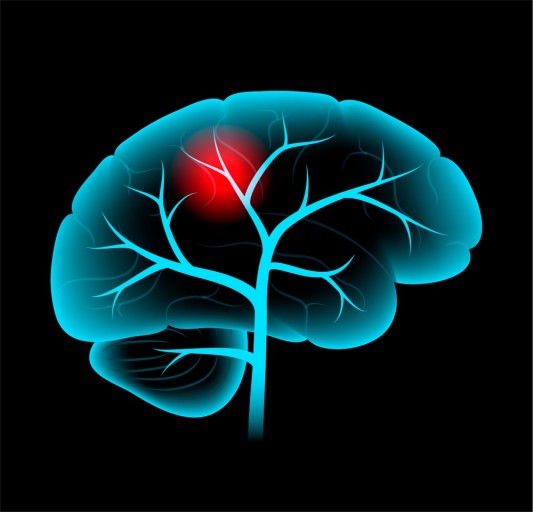

평소 경험해보지 못한 칼로 찌르듯 심한 두통,

전조 없이 갑자기 시작되는 극심한 통증이 나타난다면

뇌출혈의 초기 신호일 수 있습니다.

특히 구토나 의식 혼탁이 동반된다면 즉시 병원에 가야 합니다.

위의 증상들이 **짧게 나타났다가 사라지는 경우(TIA, 일과성 허혈 발작)**가 있습니다.

이 경우 “지나갔으니 괜찮다”고 넘기면 안 되고,

48시간~일주일 내에 본격적인 뇌졸중이 올 수 있으니 즉시 병원 진료가 필요합니다.

- 전조증상이 하나라도 보이면 즉시 119 또는 응급실 내원이 가장 중요합니다.

- 시간이 생명입니다.

뇌졸중 치료의 황금 시간대는 증상 발생 후 3시간 이내입니다. - 미니중풍(TIA)도 반드시 검진을 받아야 하며,